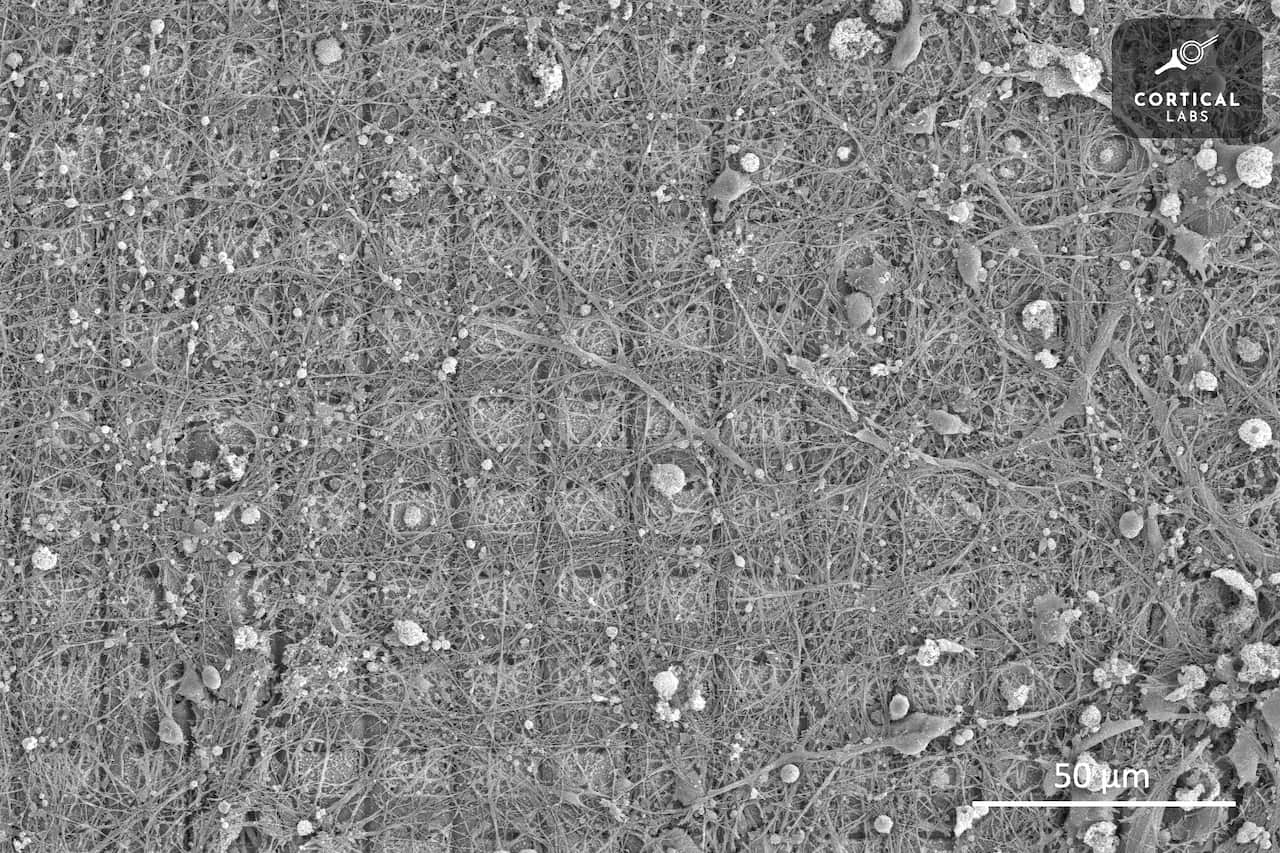

80万个脑细胞放在培养皿中,电子屏幕上是1970年代电子游戏Pong。将脑细胞放置在微电极射线(一束电子传感器)上,连接游戏,几分钟后脑细胞便开始自行组织、建立网络,学习玩游戏。

“碟中之脑”——培养皿中的脑神经元——听来与充满哲思辩论和科幻色彩的“缸中之脑”类似,而这似乎也为这一研究项目蒙上了一层超现实色彩。

张汉文创立的生物计算研究机构Cortial Labs与墨尔本蒙纳士大学共同参与了此项研究。他对SBS普通话说,Pong这个游戏实际上颇有些为难“碟中之脑”。

“但我们需要做的就是在统计学上证明,这是真实的——当给予培养皿中的细胞正确的刺激时,它们可以执行智力认知任务。”

他将这一令人兴奋的时刻定为本次实验的“尤里卡时刻”(顿悟、突破的时刻),并表示虽然早期研究成果看上去非常“科幻”,但可以延申到许多医药领域的进一步临床实验当中。

“我猜这在未来的一些应用可能是在新药和治疗方法的开发领域,特别是对那些影响大脑的疾病,例如癫痫、帕金森、阿尔茨海默症、脑退化和记忆丧失,甚至可能还有情绪障碍,如抑郁症和焦虑症。”

“这是一个方面。但我个人认为还有一个潜在发展方向,叫做个性化医疗的领域,特别是使用干细胞疗法。我们实际上可以开始专门为个人定制药物……为某人带来最好的效果和最小的副作用。”